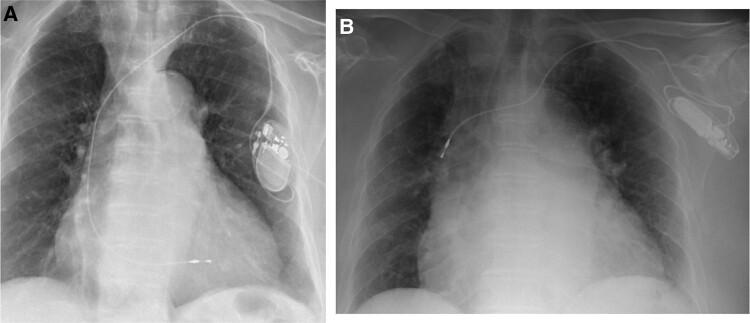

Twiddler syndrome (TS) is a complication of cardiac implantable electronic device (CIED) implantation, caused by the deliberate or unconscious manipulation of the device by the patient himself, which results in dislocation of the leads by retraction towards the subcutaneous pocket.

This report describes two clinical cases that occurred in our centre, for which two different solutions were successfully implemented. In the first case, a complete removal of the stimulation system was performed, and a leadless pacemaker (PM; Medtronic Micra VR) was implanted. In the second case, the patient underwent a revision procedure. The PM was disconnected, and the electrodes were debrided, a submuscular pocket for the PM was created, and at the end of the procedure, the PM was anchored to the pectoralis major.